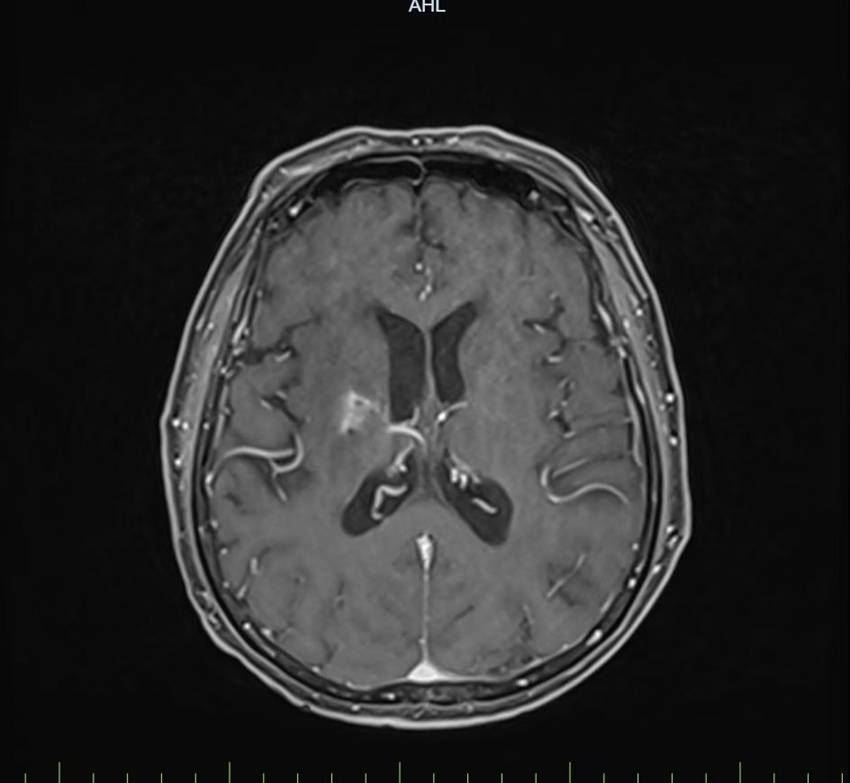

治疗过程中,团队依托3.0T头颅磁共振成像(MRI)精准定位,聚焦病灶区域实施精准放射治疗,最大限度保护正常脑组织,迅速解除神经压迫。同时,同步推进平喘、化痰、抗炎、抗真菌、输血纠正贫血等对症支持治疗,全程密切监测血常规、肝肾功能及电解质水平,确保治疗安全与患者耐受度。

治疗前后病灶对比明显缩小

放疗进行至半程时,复查MRI显示:病灶及周围脑组织水肿范围明显缩小,中线结构完全复位。患者也从最初卧床无法活动,逐步实现搀扶站立,最终平稳独立行走。